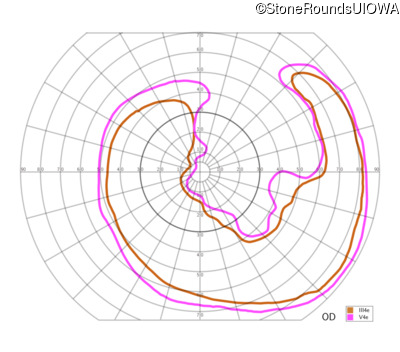

The clinical features supporting the diagnosis of Bardet Biedl syndrome in this patient include: bone-spicule-like pigmentation, narrowed arterioles and macular atrophy on ophthalmoscopy; photoreceptor loss on OCT; ulnar polydactyly, obesity, abnormal cognition, hypertension; and, normally sighted parents.